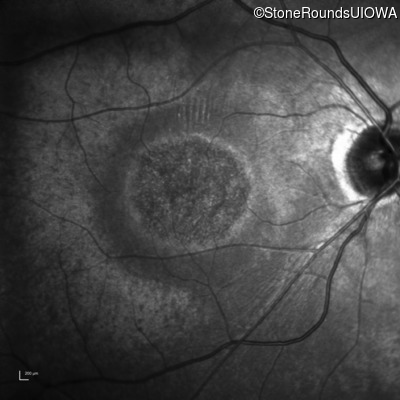

Infrared Fundus Photograph - Right - 20/60 sc

Exemplar

Infrared Fundus Photograph - Left - 20/100 sc